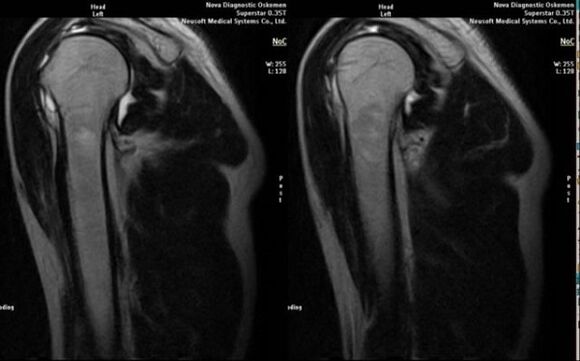

- resonancia magnética e tomografía computarizada;

Os signos que indican directamente o desenvolvemento da artrose son a aparición dun estreitamento significativo do espazo articular, a esclerose das estruturas subcartilaxinosas, o adelgazamento da propia capa de condrocitos, a aparición de osteofitos e a deposición de cristais de sal no líquido intraarticular.